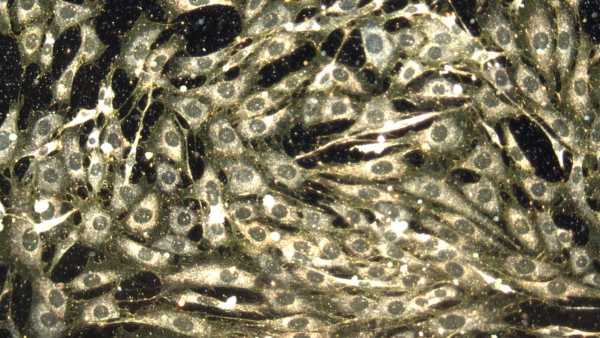

Щоб вивести більш гуманізованих мишей, дослідники спочатку вивели мишей, генетично модифікованих для ослаблення імунної системи. Коли мишам було приблизно 1-2 дні, команда ввела людські стовбурові клітини в серця тварин. Стовбурові клітини, які були вилучені та очищені з пуповинної крові, були здатні перетворитися на будь-який тип імунних клітин.

Потім серця тварин перекачували стовбурові клітини в м’яку губчасту тканину в кістках мишей, відому як кістковий мозок, де зазвичай виробляються імунні клітини. Оскільки миші мали імунодефіцит, людські стовбурові клітини могли легко закріпитися в кістковому мозку.